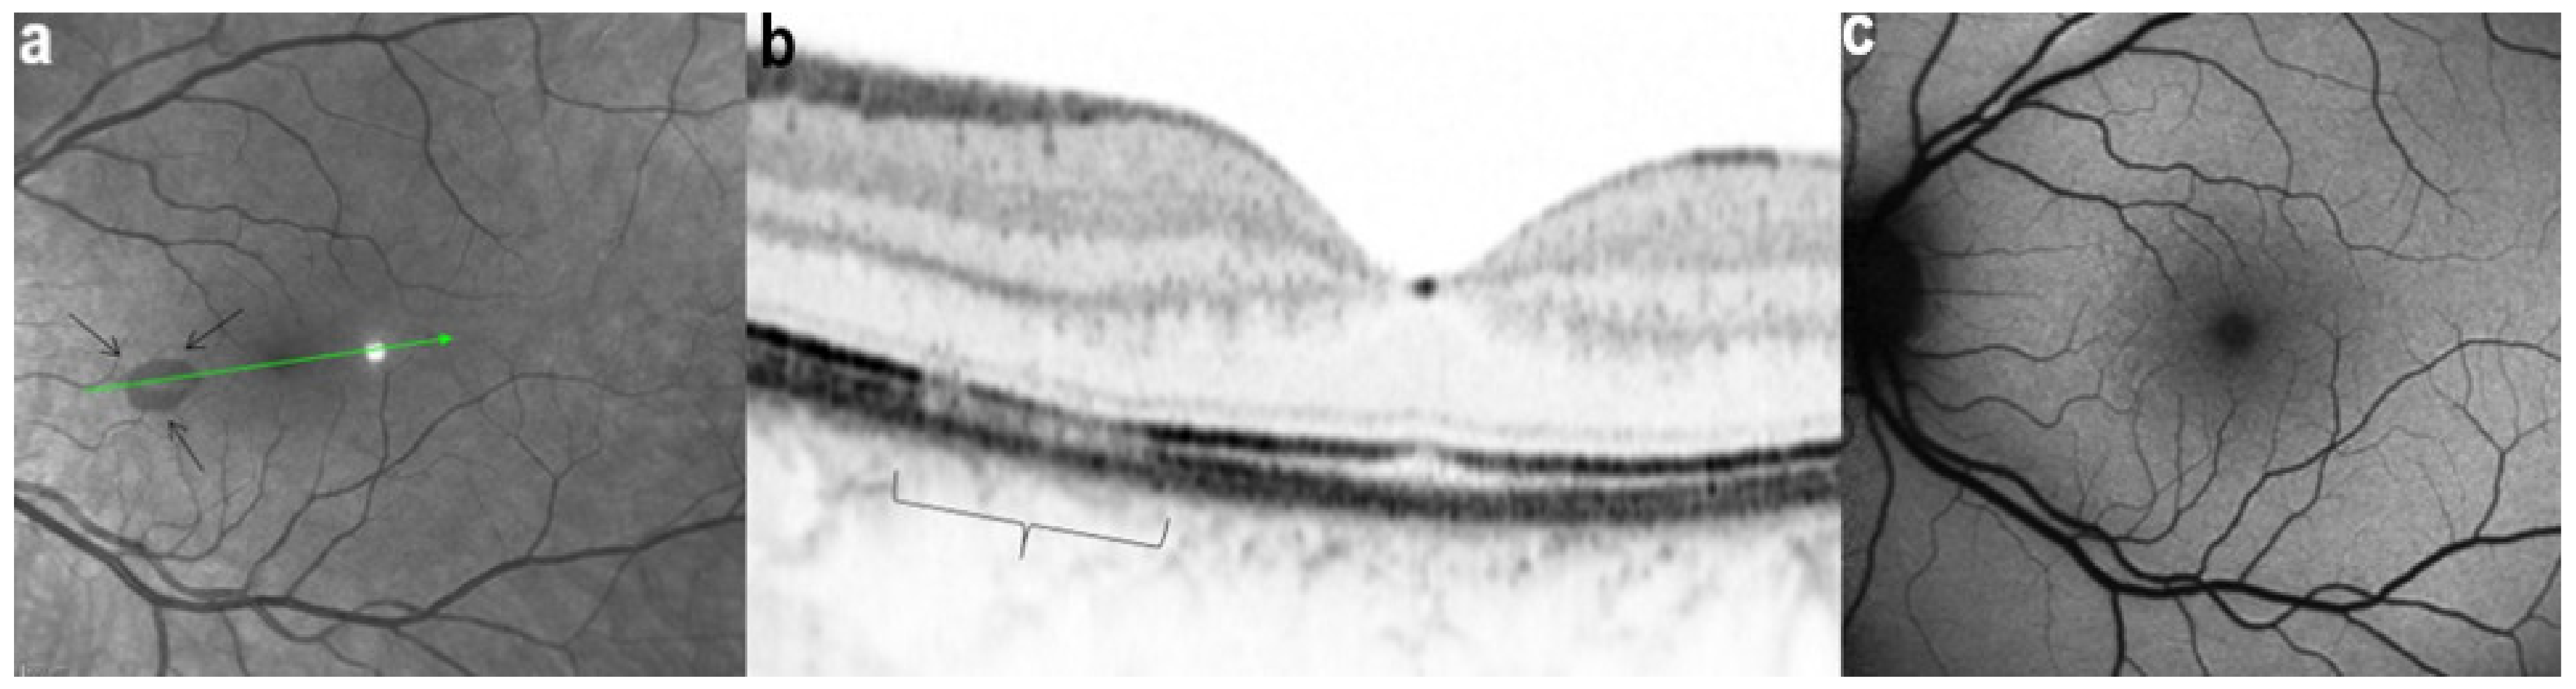

Figure 31.

AMN. NIR-R, SD-OCT and FAF images at eight days after the onset of symptoms. (a): NIR-R imaging shows a sharply oval hyporeflective area (arrows) corresponding, on SD-OCT (b), to an attenuation of the EZ whereas the IZ is not seen (b, bracket). (c): BAF signal is normal.

Figure 32.

AMN. NIR-R, SD-OCT, FAF, FA, and ICGA images at first presentation. NIR-R and SD-OCT images: NIR-R imaging shows hyporeflective petal-like oval areas in the macular region (arrows) in corresponding on SD-OCT to a reduction of the signal of the IZ (brackets). In OD, the reduction of the signal is limited to two segments of the outer retina, while in OS, it comprises the whole outer retinal section corresponding to the hyporeflective infrared lesion.